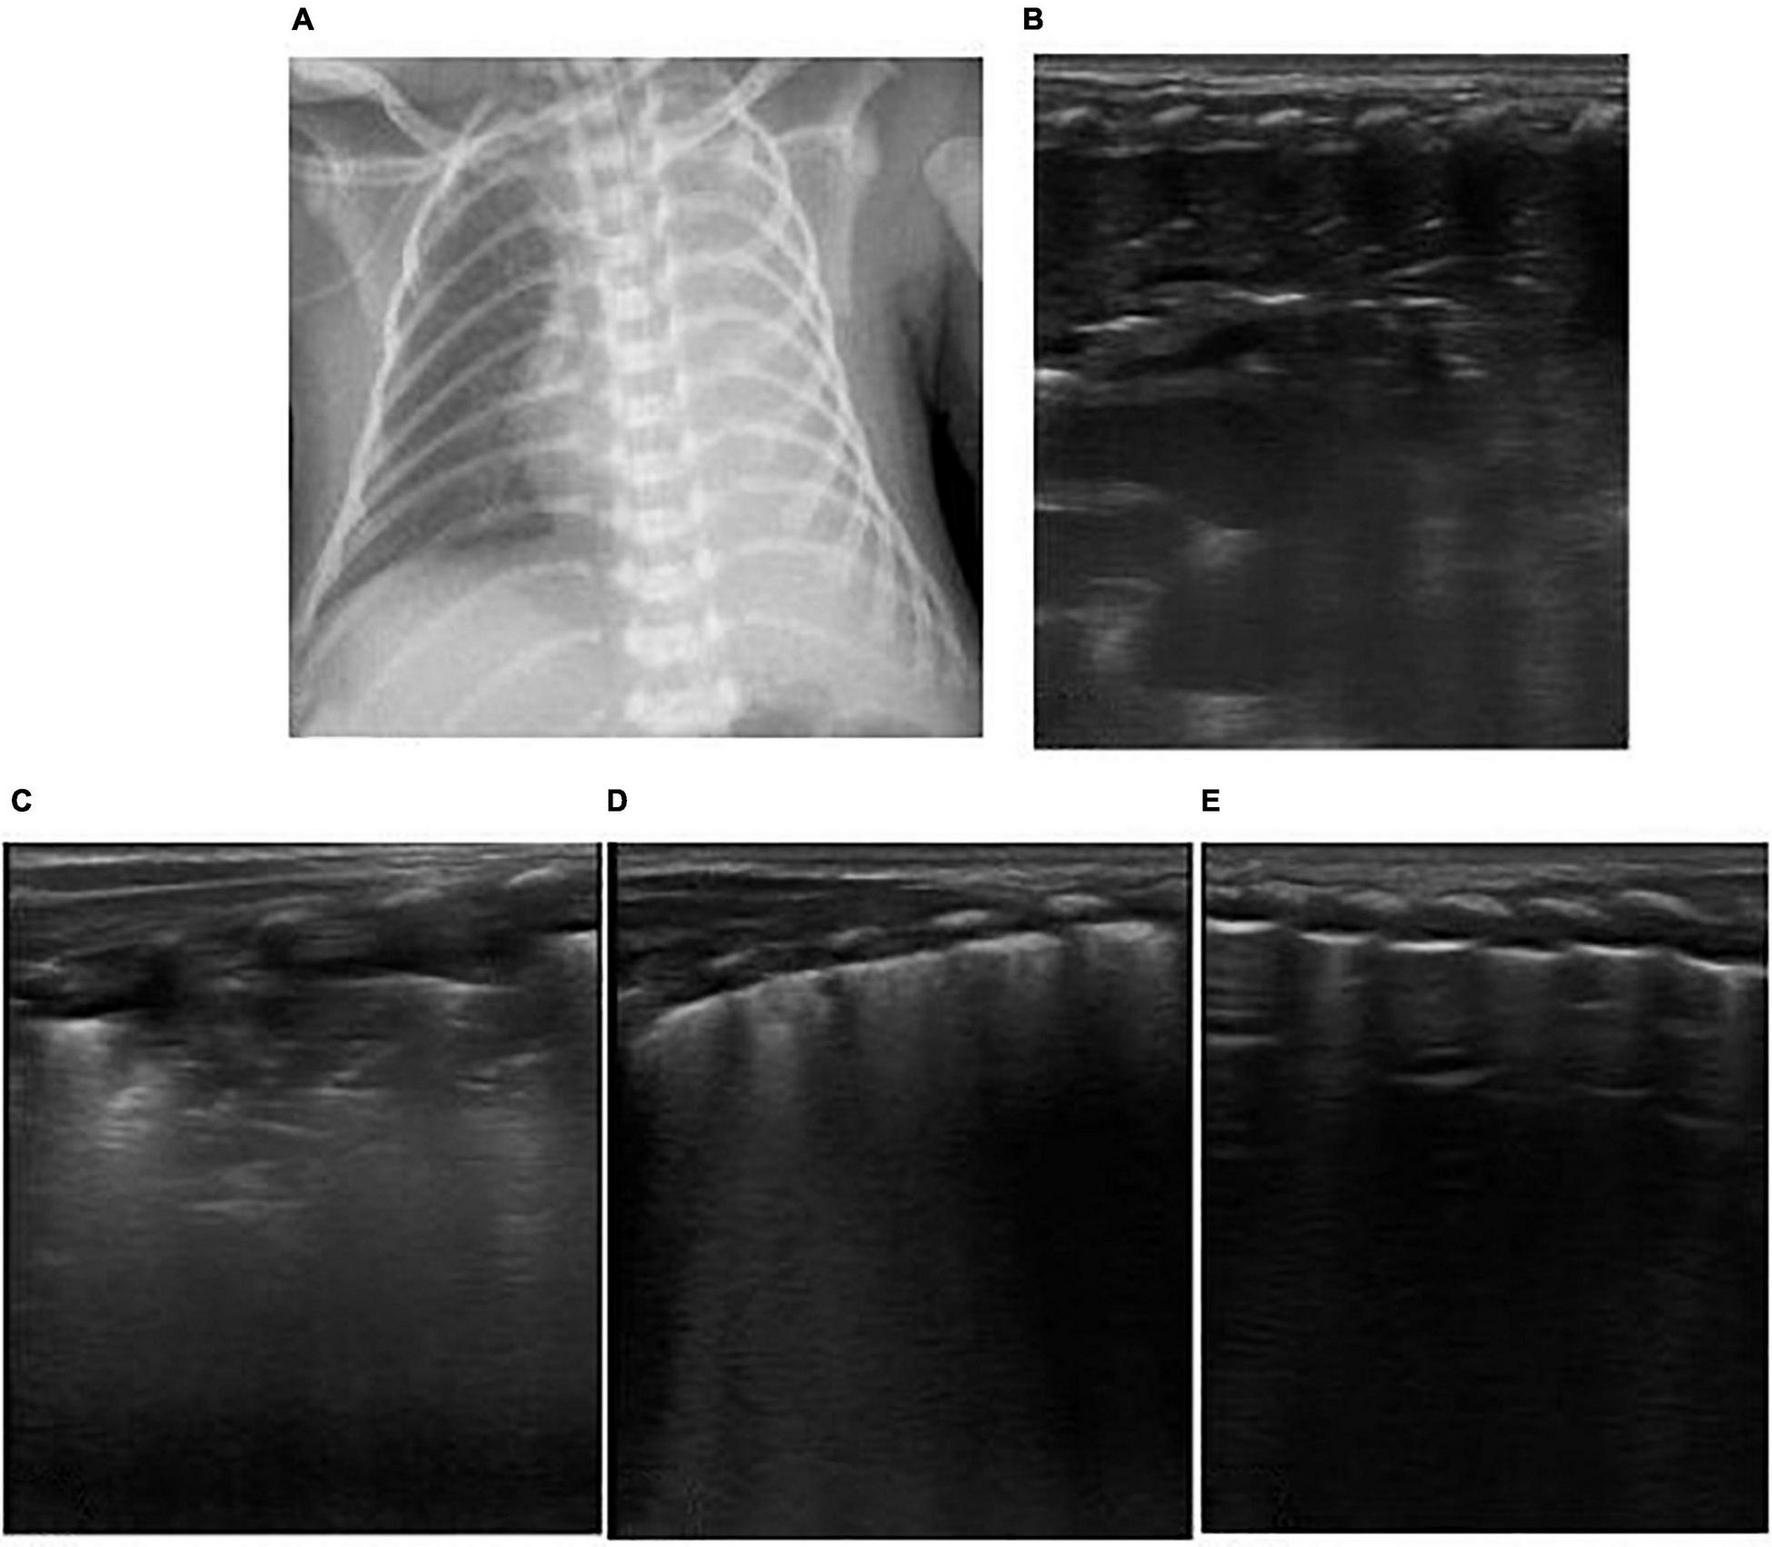

FIGURE 4

The patient was born at 39 weeks of gestational age by natural delivery. The amniotic fluid was III turbid, and the Apgar score of 1, 5, and 10 min of birth were 2, 3, and 6 points. Respiratory distress occurred after birth and requiring mechanical ventilation. It was diagnosed as neonatal meconium aspiration syndrome. Under mechanical ventilation, man-machine incongruity appeared. The patient had weakened breath sounds in both lungs, a heart rate of 120 beats/min, dull heart sound, pale skin tone, cool limb ends, and weak radial artery beats. The blood pressure was 56/35 mmHg, and the shock score was 5 points. Continuous hypoxemia appeared, the arterial blood gas was PO2 30.4 mmHg, and calculated Oxygenation index (OI) value was 50. Emergency bedside ultrasound revealed the lung slip of both lungs disappeared and without B-line, stratospheric sign showed, and the lung point was not explored, suggesting the diagnosis of massive pneumothorax on both sides (A). Emergency thoracocentesis was performed under ultrasonic monitoring. After the operation, the blood oxygen saturation increased, blood pressure rose to 65/40 mmHg and the heart sound was strong. After 30 min, the X-ray operator at the bedside arrived, and the X-ray chest film showed bilateral pneumothorax (B). In emergency situations, bedside ultrasound is easier to obtain than X-ray examination. In the figure, who has massive pneumothorax on both sides, hours after thoracic puncture and drainage, the baby appeared to cyanosis, the breath sounds in both lungs was weak, the heart rate increased to 180 beats/min. Reexamination of LUS showed that pneumothorax decreased and the lower boundary of lung was too low, bedside cardiac ultrasound showed inferior vena cava expansion and fixation (C), ventricular filling and relaxation limitation (D), suggesting that the patient had excessive lung expansion. The ventilator pressure was reduced to increase the returning blood volume, and the heart rate decreased gradually to 150 beats/min. Ventricular filling and diastolic improvement were observed by ultrasound (E).

Atelectasis is a common complication of neonatal lung diseases, usually accompanied by NRDS, MAS, severe pneumonia, and other diseases. It is also the common cause of neonatal dyspnea. Neonates given mechanical ventilation often face man-machine incongruity or disengagement failure caused by atelectasis. Lung recruitment refers to a sustained increase in airway pressure or volume within a limited time to maximize the physiological expansion of the maximum lung units, with the goal to open the collapsed pulmonary alveoli, thus improving gas exchange, oxygenation function, and lung compliance. The ultrasound of neonatal atelectasis was characterized by hepatoid echo consolidation accompanied by lung pulsation and air bronchogram (9, 10), indicating serious alveolar collapse. With the increase in alveolar pressure during lung recruitment, alveolar inflation increased, and ventilation and blood flow ratio improved. Under LUS monitoring, dynamic air bronchogram increased, A-line gradually appeared, and B-line and consolidation decreased gradually. Moreover, changes in lung sliding were monitored, and positive pressure ventilation pressure was adjusted to avoid pneumothorax caused by alveolar overinflation (see Figures 4C–E, 5A–E).